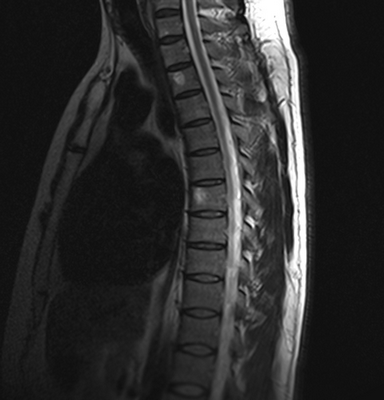

МРТ шейного отдела позвоночника: оценка лордоза, сагиттальная плоскость, Т2 последовательность

- искривления позвоночника - кифоз, лордоз, сколиоз;

- дегенеративно-дистрофические заболевания - остеохондроз, остеоартроз, спондилез и пр.;

- демиелинизирующие состояния - рассеянный склероз или иные варианты;

- аутоиммунные нарушения позвоночных сегментов, сопровождающиеся спондилитом и анкилозирующим спондилоартритом при болезни Бехтерева;

- дегенеративные патологии спинного мозга - боковой амиотрофический склероз, сирингомиелию и пр.;

- последствия травматических повреждений - переломов позвонков, вывихи, подвывихи, растяжения и разрывы связок, мышц;

- грыжу, дислокацию (смещение), разрушение дисков;

- компрессию нервного корешка или спинного мозга, стеноз позвоночного канала и пр.